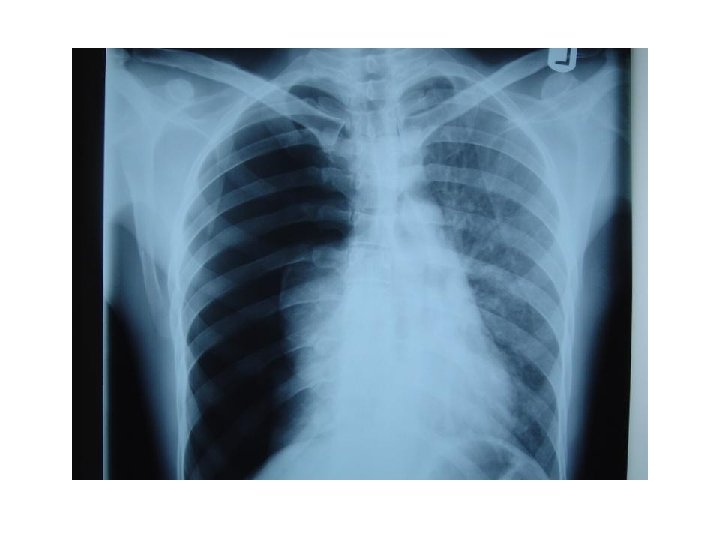

Tumors Left lower zone We say zone not lobe in X-Ray … because we can’t confirm the lobe except by other modality. . E. g. lateral Xray